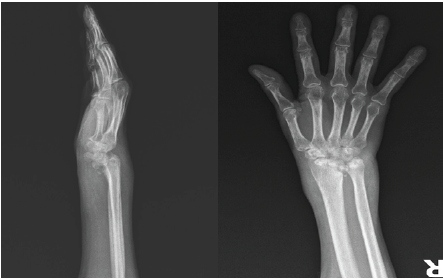

On inspection, marked swelling and erythema were observed in the right wrist compared with the contralateral side. Palpation revealed significant pain and tenderness over the wrist joint. Distal neurovascular and motor examinations were unremarkable. Range of motion assessment demonstrated limitation of wrist extension to 15° and flexion to 45°. Plain radiographs revealed joint subluxation, severe degeneration of the carpal bones consistent with osteomyelitis, narrowing of the radiocarpal and radioulnar joint spaces, and diffuse arthritic changes. According to the Eaton Littler Classification system, our patient’s wrist joint degeneration was grade 4 [5]. The patient was evaluated postoperatively at 15, 30, 45, and 60 days. At each follow-up visit, progressive improvement in pain and tenderness was noted, and pain on weight bearing had completely resolved.

A two-stage surgical approach was employed for wrist arthrodesis. In the first stage, a volar (Henry) approach was used to excise all necrotic bone and soft tissue affected by osteomyelitis, and tissue samples were obtained for culture (Figure 1).

Figure 1: Pre-operative wrist joint degeneration.